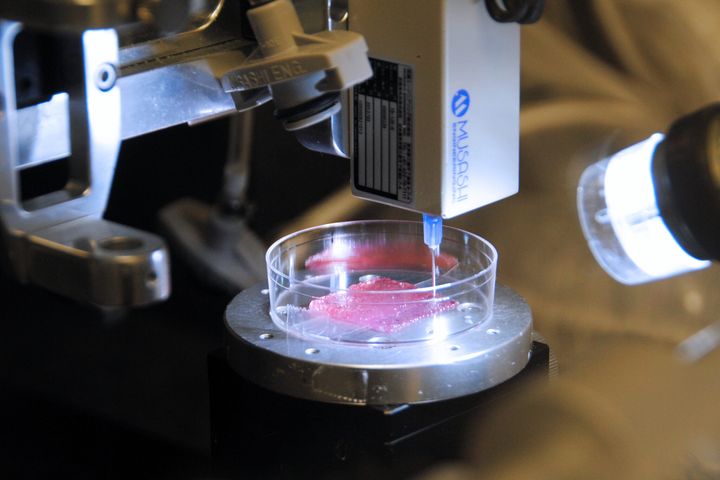

Breakthrough in 3D Bioprinting: Fat-Based Tissue Engineering for Wound Healing

Researchers have developed a method to 3D bioprint tissue in a way that can heal wounds.